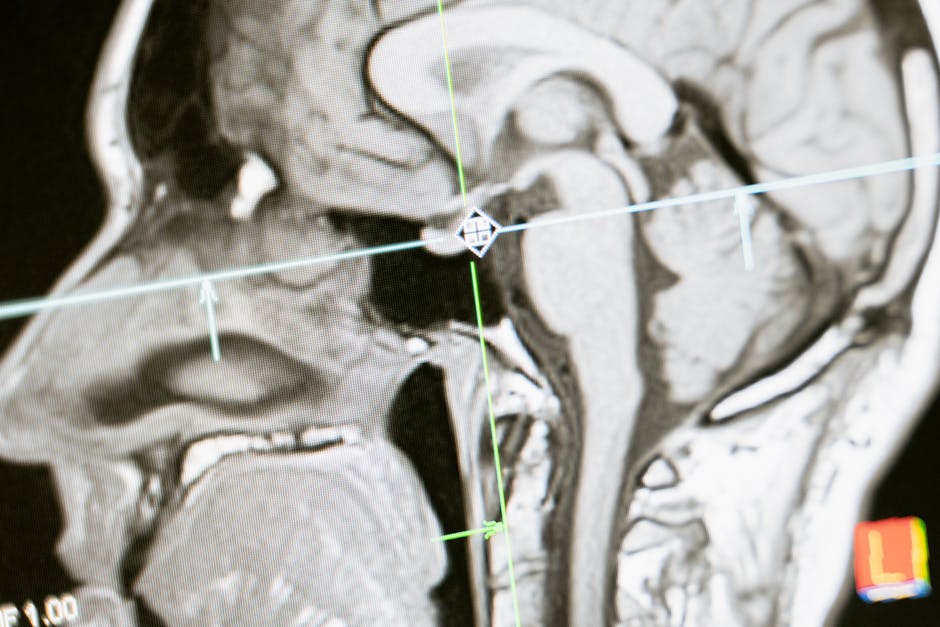

Risonanza magnetica sagittale del cervello umano, visualizzazione dettagliata per indagine neuroscientifica e studio del funzionamento cerebrale.

Foto fornita da Pexels

2. Raccolta dei dati: Utilizzare strumenti adeguati come risonanza magnetica funzionale (fMRI) e elettroencefalogramma (EEG) per monitorare l'attività cerebrale.

3. Applicazione di tecniche neuroscientifiche: Utilizzare strumenti come la risonanza magnetica e l'EEG per raccogliere dati sull'attività cerebrale.

2. Scelta delle tecniche: Determinare quale strumento, come la risonanza magnetica funzionale o l'EEG, è più adatto per il tipo di dati richiesti.

Qual è il ruolo della risonanza magnetica e dell'EEG nella ricerca neuroscientifica?+

La risonanza magnetica funzionale (fMRI) e l'elettroencefalogramma (EEG) sono strumenti cruciali per monitorare e analizzare l'attività cerebrale, fornendo dati sulle funzioni cognitive e sulle risposte comportamentali a differenti stimoli.